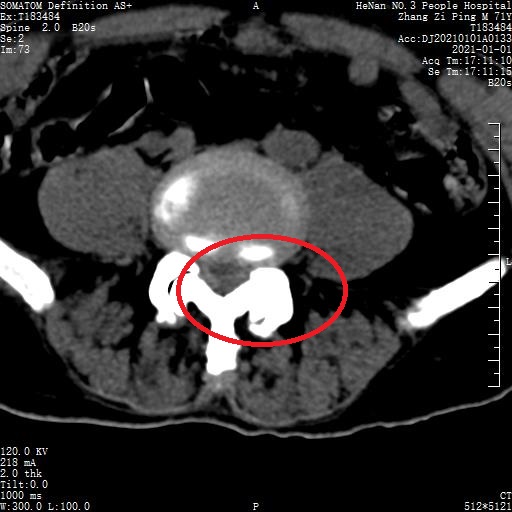

1623149373279880.jpg

术前 MRI 2